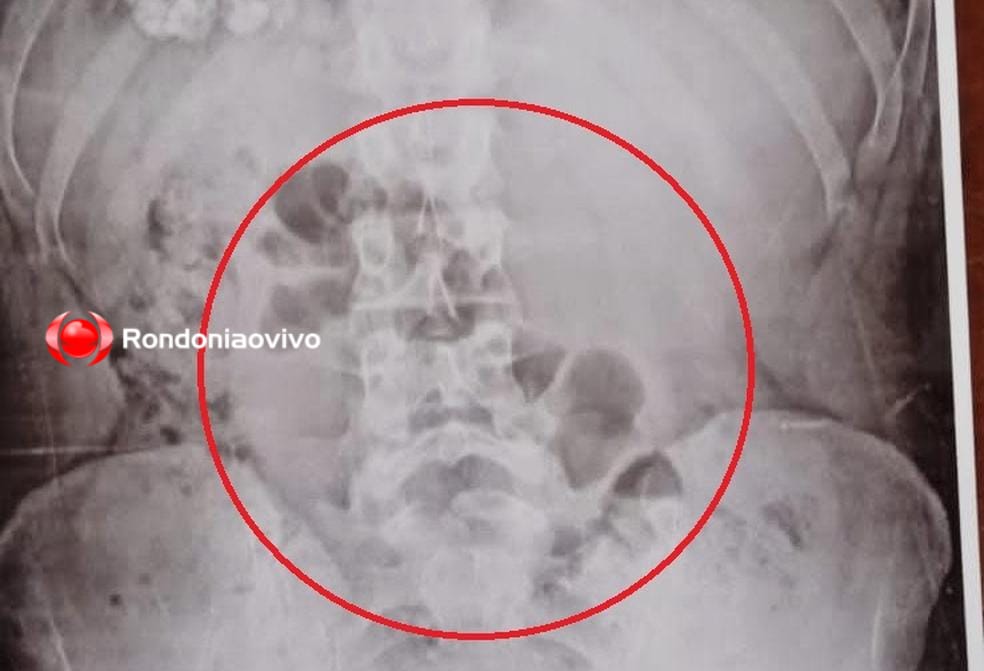

Mulher foi descoberta com a droga no estômago durante revista através do equipamento de raio-X

Estava indo visitar um apenado que cumpre condenação no presídio e alegou que levava a droga para ele

Ela estava com cocaína e maconha introduzidas ao corpo